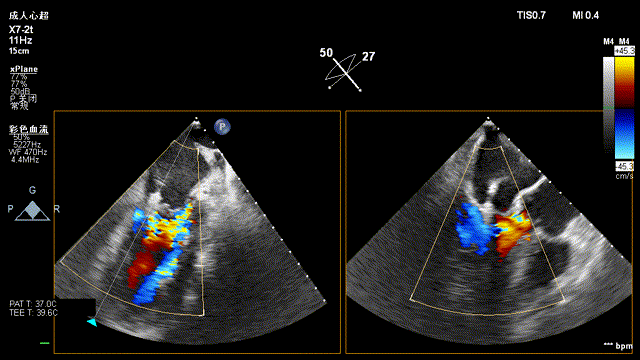

复查超声显示主动脉瓣架深度合适、位置稳定,瓣叶启闭正常,未见明显瓣周反流:

二尖瓣反流较术前显著减少: